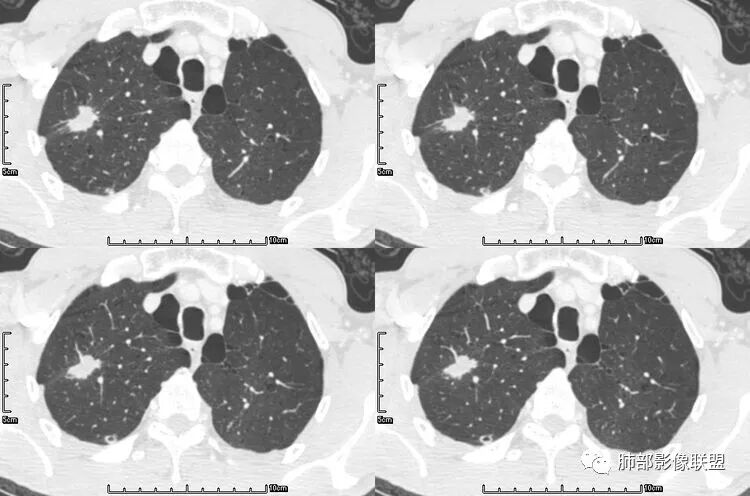

空洞型肺转移瘤成因尚不完全明确, 可能与鳞癌中心角化物排空 、腺癌黏液样退变后黏液排空 、肿瘤血供不足引起坏死 、肿瘤继发脓肿 、化疗等机制有关,其中部分薄壁囊腔样结可能是肿瘤细胞沿着原有的肺大泡或其它囊性结构生长或者肿瘤向小支气管侵犯引起活瓣性阻塞而形成 ,但无一种机制能解释全部现象。空洞或囊腔大小并不反映病情变化, 其临床意义不大, 而瘤灶的数目及大小, 特别是瘤灶实性成分的多少才可能更准确反映病情变化。肺癌形成空洞与其肿瘤本身性质有明显联系,肿瘤分化程度差,倍增时间越短,恶性程度越高,组织液化坏死形成空洞倾向越明显;鳞癌空洞偏大,内缘不规则,常易形成X线平片中癌梁样改变与CT中壁结节样改变;而腺癌空洞大小不定,洞内分隔明显,内缘不规则,且较难于形成壁结节等改变;合伴空洞的肿瘤边缘情况也对判断肿瘤性质有帮助。

其中囊样空洞和小环形空洞属于薄壁空洞,泡样空洞和不规则空洞属于厚壁空洞,其中腺癌空洞型肺转移瘤主要表现为小环形空洞,以下3个病例均表现为小环形空洞的转移瘤:

本病例左肺下叶肿块,有深分叶、毛刺、胸膜牵拉凹陷、支气管截断及纵隔内淋巴结肿大等征象,都均支持病灶为恶性,如腺癌,而且叶间裂的多发结节也提示是腺癌来源可能大;双肺多发结节、肿块,大部分病灶有分叶、毛刺及胸膜凹陷的恶性征象,与原发肿瘤本身的性质有关,所以应该与左肺下叶肿块同源,而且双肺多发病灶内空洞也具有多样性;

此病例中空洞形态多样,内壁不光整,有分隔影,周围未见明显卫星灶及钙化灶,结核不太符合;患者病史慢性病史,无明显发热,缺乏中毒临床表现,急性感染基本排除;各种中性粒细胞胞浆抗体阴性,没有鼻窦炎,肾脏等病史,基本排除血管炎;霉菌性空洞常见于免疫机能低下者, 常为空洞、肺炎、伴“ 晕圈”征的结节及支气管扩张合并存在。